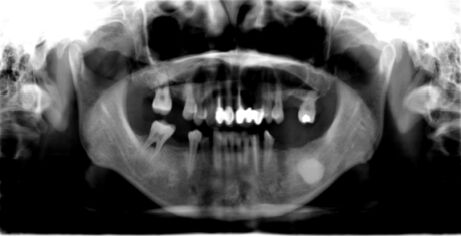

43.一位 12 歲青少年,無意間發現右臉頰無痛腫脹的情形,經環口放射線影像檢查 (panorex),於右側下顎骨呈現一處多室性病灶(如下圖所示)。有關此例之診斷推論,下列那一項最不合理? (A) 若其右側下齒槽神經支配區域有麻木現象,可以合理懷疑為造釉細胞瘤(ameloblastoma) (B) 以針頭抽吸(needle aspiration)呈現淡黃色清澈液體,可以懷疑為含齒性囊腫(dentigerous cyst) (C)以針頭抽吸(needle aspiration),初期呈淡黃色清澈液體,繼而呈現淡紅色液體,則應可 懷疑是 aneurysmal bone cyst (D) 由其右側下顎第一大臼齒牙根型態來看,有明顯病理性吸收之現象